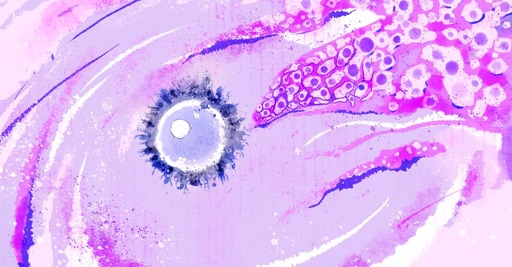

Jak niedawno wykazali badacze, komórki jajowe można stworzyć na przykład z komórek skóry. Po co są prowadzone takie eksperymenty?